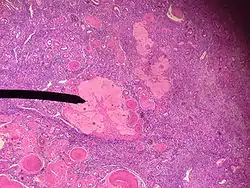

The corpus albicans (Latin for "whitening body"; also known as atretic corpus luteum, corpus candicans, or simply as albicans) is the regressed form of the corpus luteum. As the corpus luteum is being broken down by macrophages, fibroblasts lay down type I collagen, forming the corpus albicans. This process is called "luteolysis". The remains of the corpus albicans may persist as a scar on the surface of the ovary.

The corpus luteum normally grows to about 1.5 centimeters in diameter, reaching this stage of development 7 to 8 days after ovulation. Then it begins to involute and eventually loses its secretory function and its yellowish, lipid characteristic about 12 days after ovulation, becoming the corpus albicans;[1] during the ensuing few weeks, this is replaced by connective tissue and over months is absorbed.[2]